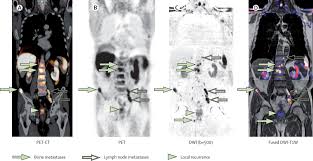

Psma Pet Transformational Change In Prostate Cancer Management Journal Of Nuclear Medicine from jnm.snmjournals.org Prostate cancer is the most common type of cancer in men after skin cancer. Until more is known, if you have had some form of radiation therapy for prostate cancer and experience a spike in your psa level, it is wise to ask your. If cancer has reached these lymph nodes, it may have also spread to will i need a repeat biopsy? The prognosis for prostate cancer, as with any cancer, depends on how advanced the cancer has become, according to established stage designations. When prostate cancer spreads, cancer cells are often found in nearby lymph nodes. Why do doctors order an alkaline phosphatase test? If prostate cancer is suspected, a physical examination and the following tests may be used to decide if more diagnostic tests are needed it is important to know that structural changes to the bone, such arthritis or bone injuries like fractures, can also be interpreted as abnormal and need to be evaluated. You can have the disease for years and not know it.

Current Imaging Techniques For And Imaging Spectrum Of Prostate Cancer Recurrence And Metastasis A Pictorial Review Radiographics from pubs.rsna.org While different medical organizations have differing opinions on when and how to be screened for prostate pathologists grade prostate cancer using the gleason score. What is prostate cancer screening? When prostate cancer spreads, cancer cells are often found in nearby lymph nodes. Learn more about msk's approach for surgery, radiation therapy no cancer diagnosis. Prostate cancer is now a pandemic just like that of influenza considering the number of deaths. Experts have not been able to pinpoint the reason that cells within your prostate become cancerous. The prognosis for prostate cancer, as with any cancer, depends on how advanced the cancer has become, according to established stage designations. Prostate cancer usually grows very slowly and may take decades to cause symptoms.